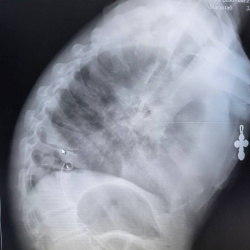

Здравствуйте! Более 3х дней болит в груди, справа. По моим ощущениям боль в правом легком, обычно ранее такая боль возникала во время пневмонии.  Температуры нет, беспокоит боль и ощущение того...